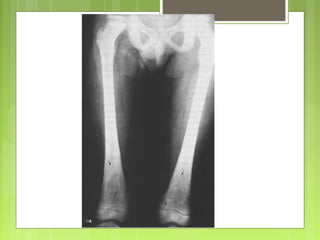

- Es un proceso muy frecuente que se encuentra en

el 30-50% de los niños de más de 2 años.

- Con frecuencia son pequeños (media 0,5 cm)

- Se cree que son defectos congénitos más que

neoplasias.

- La mayoría aparecen en la metáfisis distal del

fémur y de la proximal de la tibia y casi la mitad son

bilaterales o múltiples.

- Son asintomáticos y suelen detectarse casualmente

en la radiografía y la mayoría se resuelven

espontáneamente.

Defecto cortical

fibroso

- Lesiones similares al defecto cortical fibroso pero

de mayor tamaño (5-6 cm) y que se desarrollan en la

adolescencia.

- Pueden presentarse como fractura patológica

Fibroma no

osificante